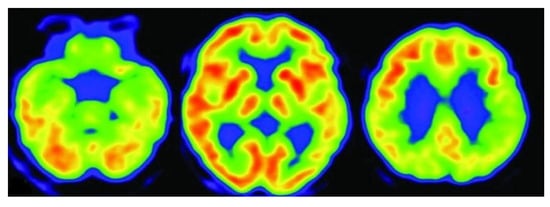

3.3. Positron Emission Tomography (PET)

3.4. Fluorodeoxyglucose Positron Emission Tomography (FDG-PET)